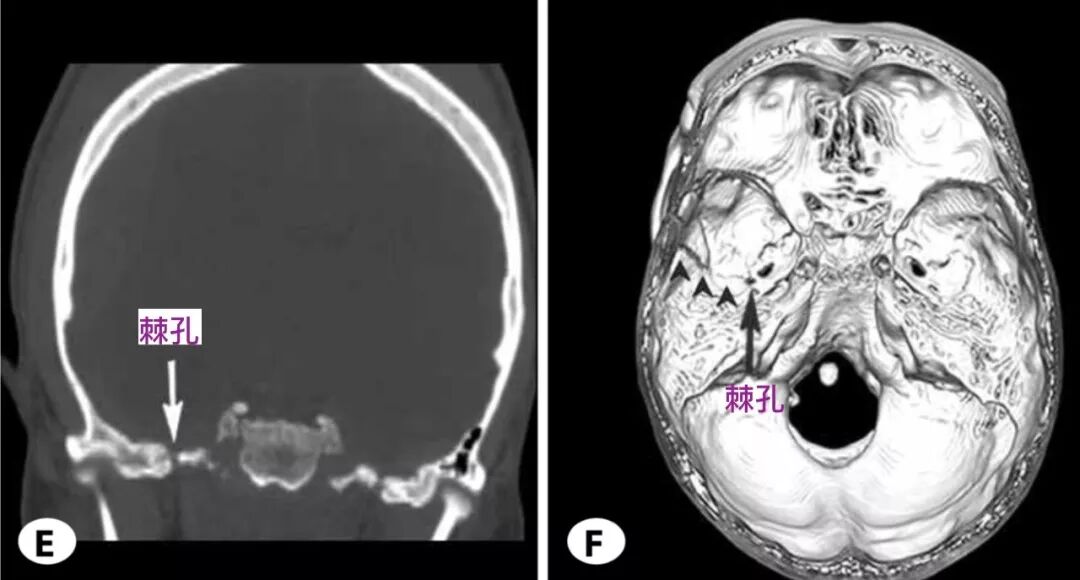

棘孔

脑血管解剖学习笔记第2期棘孔的解剖

6mm 棘孔是一短骨管,管长右侧 为7.3mm(6~14mm),左侧为 7.